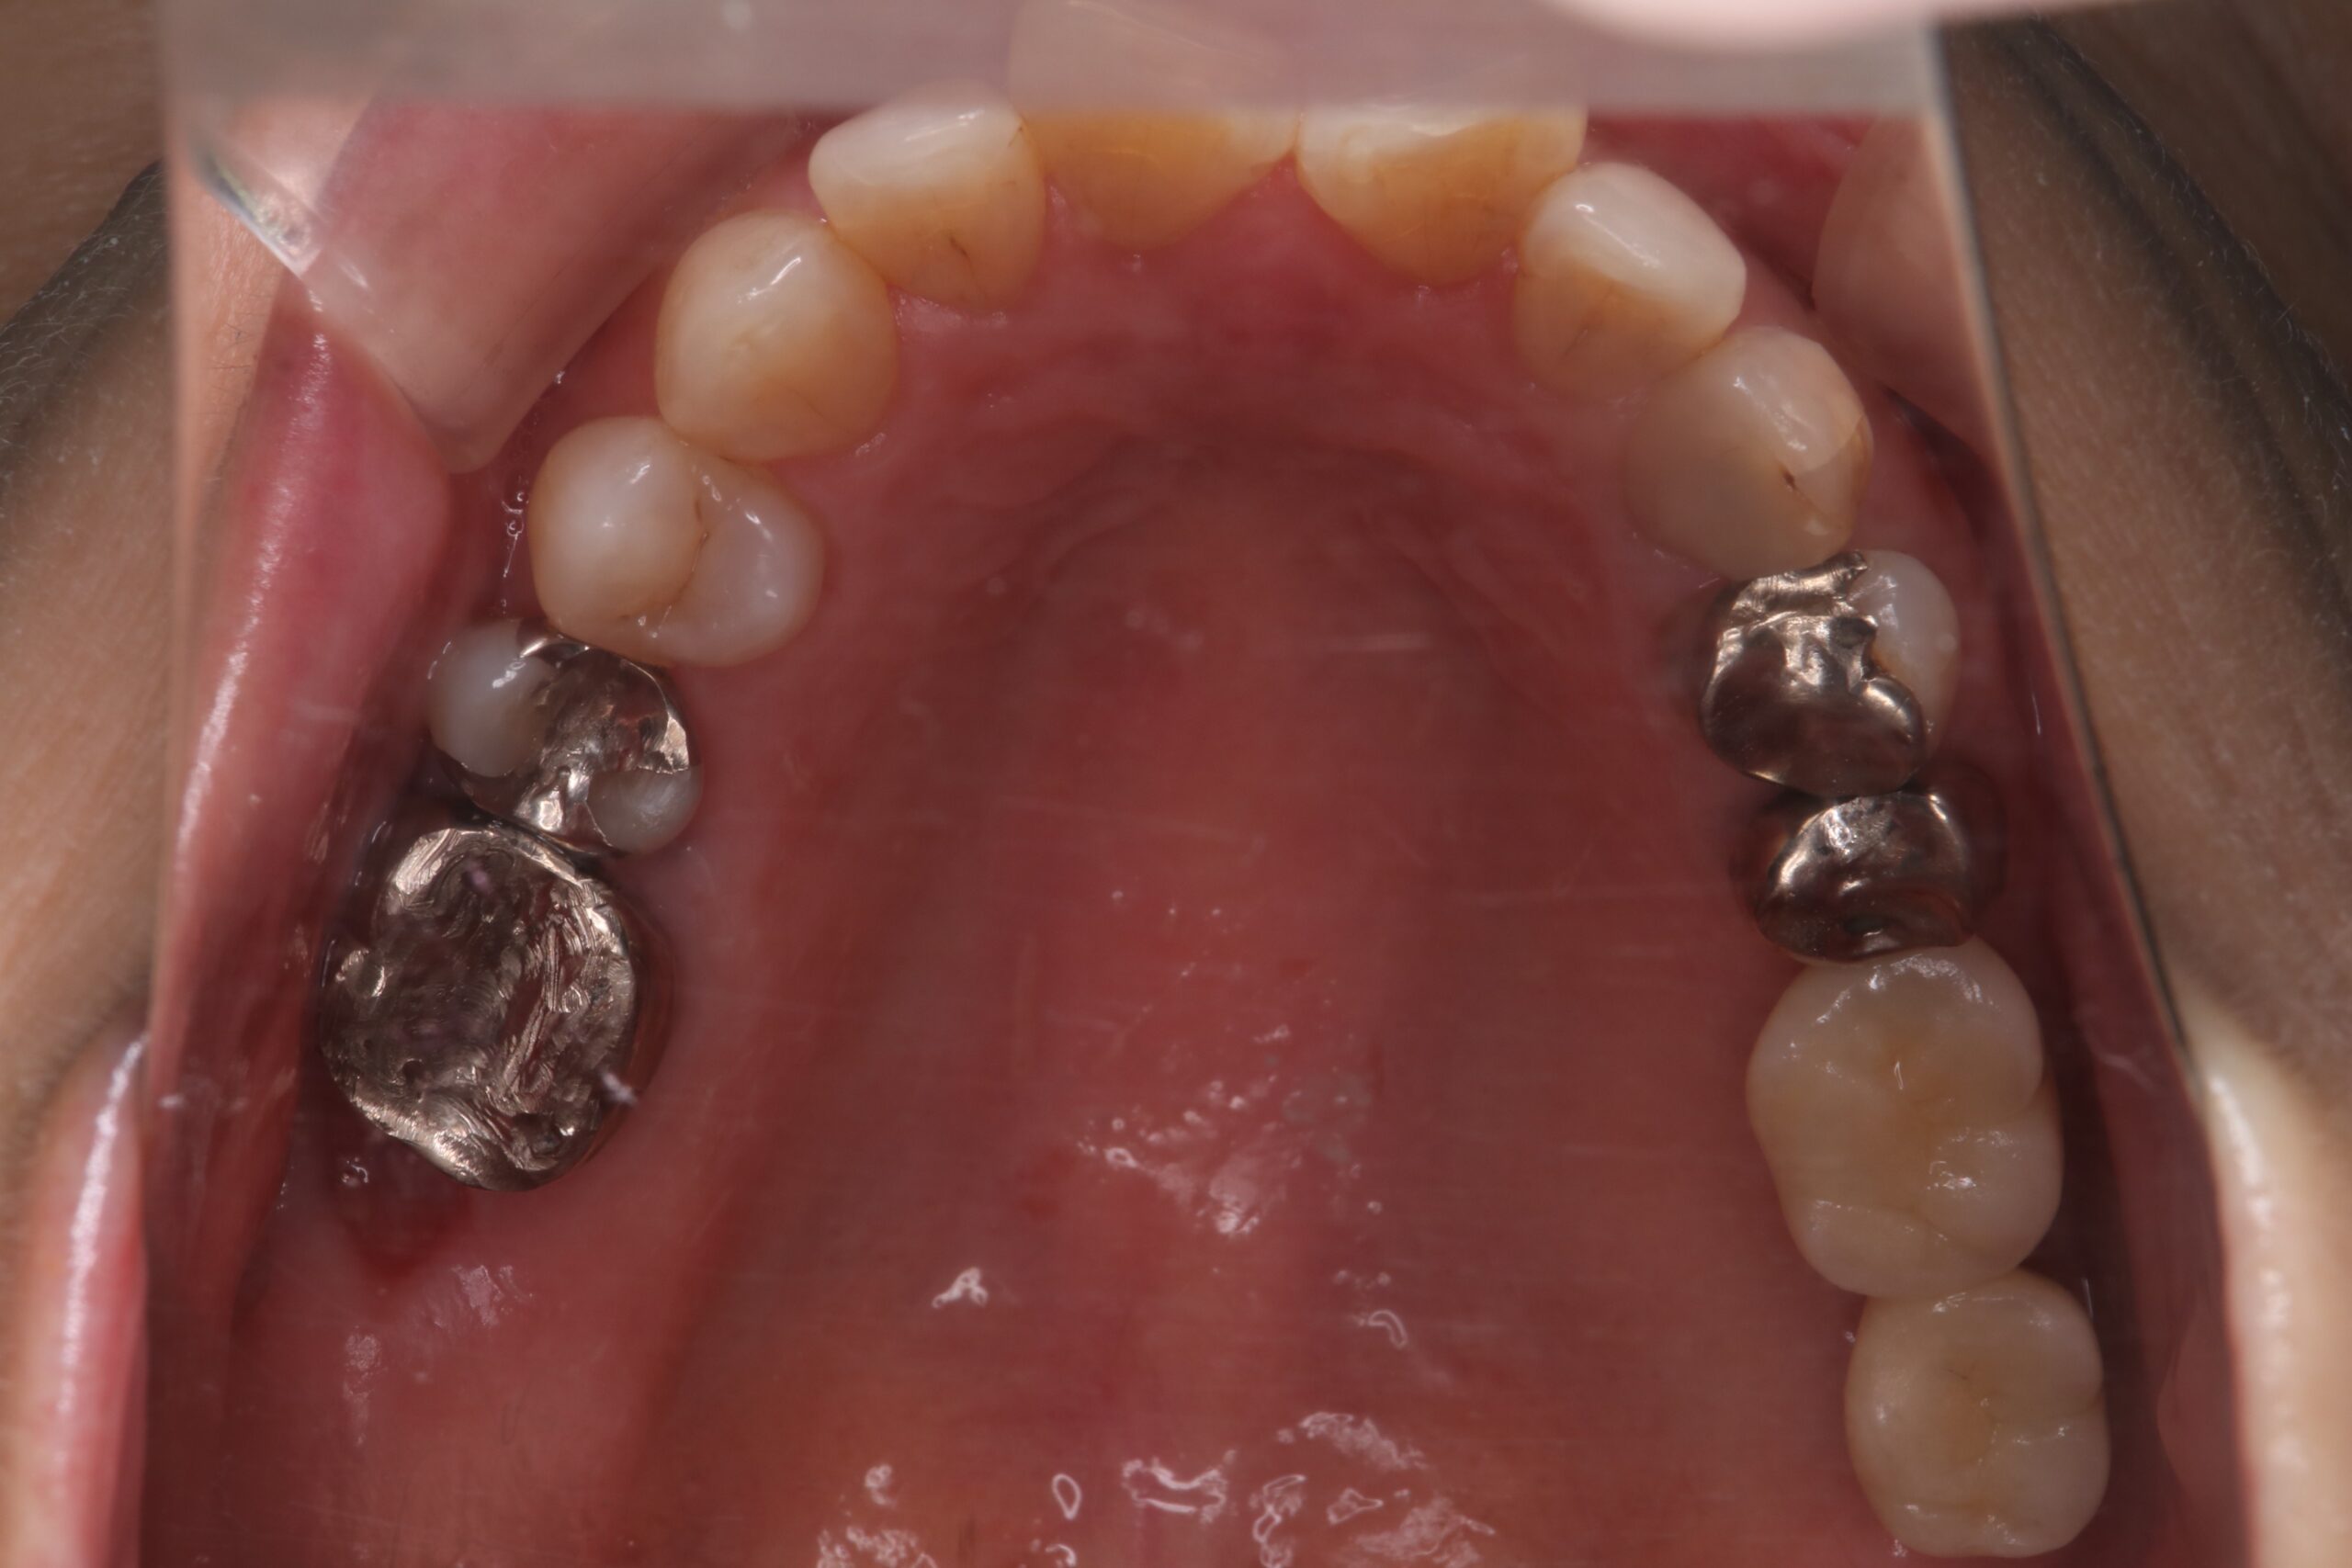

症例